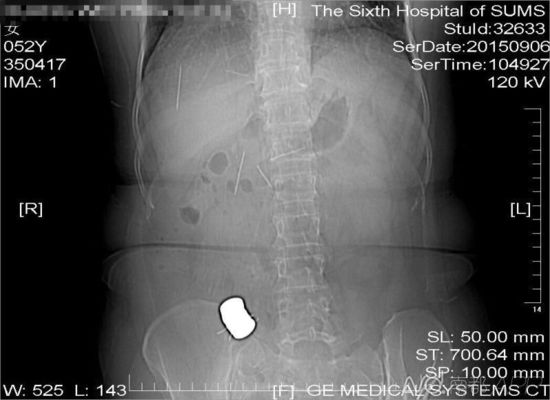

CT檢查結(jié)果中顯示,老人腹中有多個(gè)金屬異物和散落的繡花針

進(jìn)行的CT檢查結(jié)果顯示,黃姨腹中有多個(gè)金屬異物和散落的繡花針。主管醫(yī)生黃俊博士介紹,這些針分別位于黃姨小腸內(nèi),部分已經(jīng)穿出小腸散播于腹腔內(nèi),還有部分金屬異物,最大的一塊上附著了數(shù)根斷針,有一根插進(jìn)了胰腺,剩下的一根在脊柱附近,每枚約長(zhǎng)4厘米。